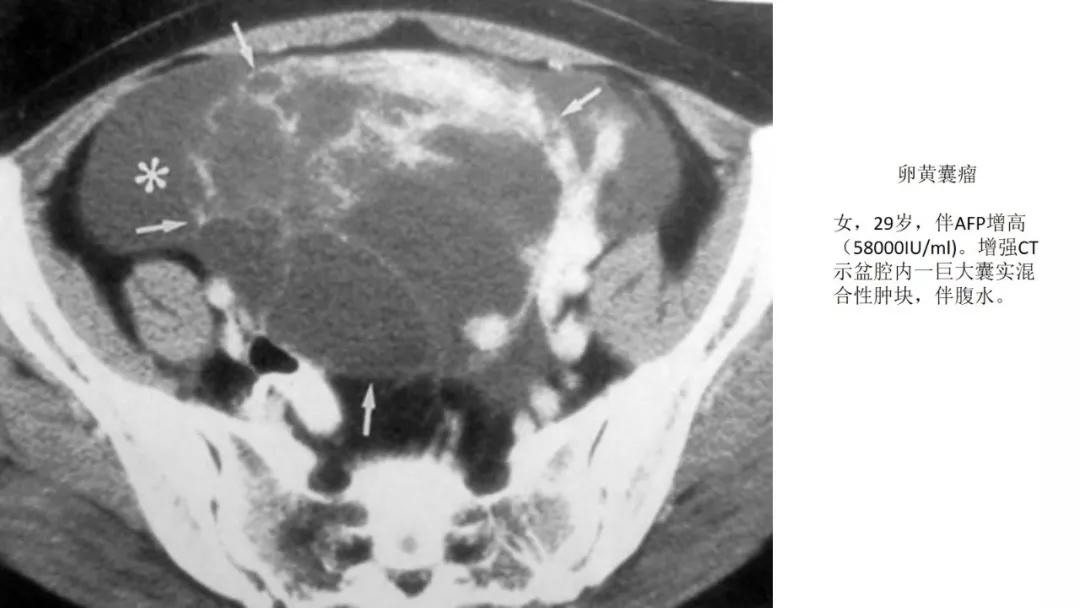

AFP升高:卵黄囊瘤、无性细胞瘤、混合瘤

恶性者常呈实性或混杂性肿块,多数边界清楚,可伴有不规则沙粒状钙化。无性细胞瘤常为实性肿块,轻度强化,内胚窦瘤实性成分明显强化,不成熟畸胎瘤呈混杂密度。结合年龄及临床生化检查,有助于诊断。